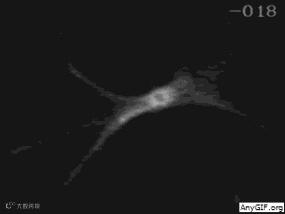

12.神经细胞与钙离子的精彩邂逅

钙离子一直都是神经细胞最重要的“信号离子”,通过显微注射技术将钙离子探针放进神经细胞中,使得探针和钙离子相互作用而产生荧光,钙信号在神经细胞中会像水波一样迅速向外扩散。